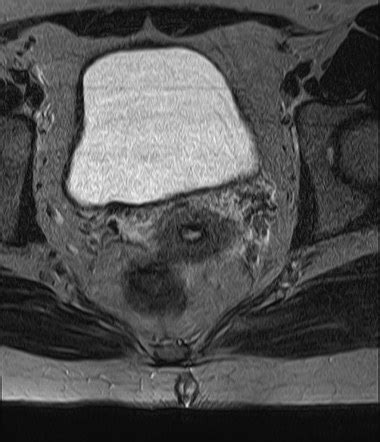

3. Magnetic Resonance Imaging (MRI)

MRI is another powerful imaging technique, but it uses strong magnetic fields and radio waves instead of X-rays. It’s particularly good at visualizing soft tissues, which makes it ideal for evaluating pilonidal sinuses . MRI offers incredibly detailed images, far better than those provided by an X-ray. It can help doctors to get an accurate picture of the sinus tract, detect any associated abscesses, and assess the involvement of the surrounding tissues. It can differentiate between inflamed tissue and fluid, making it easier to assess the extent of the infection. MRI is often used when a patient is a candidate for complex surgical procedures or when the initial treatment is not working. The ability to see soft tissues in such detail allows for better pre-operative planning. It is also a valuable tool for ruling out other conditions that might mimic a pilonidal sinus , such as a tumor. Pilonidal sinus radiology will often consider this more advanced approach.